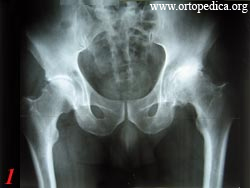

1. - Больной К. Артроз левого тазобедренного сустава 3 ст.